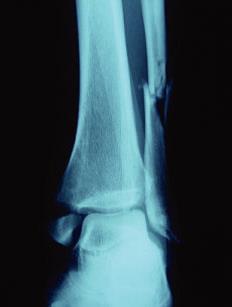

Patient consulte aux urgences après une chute, à l’examen clinique pas de luxation , oedème de la cheville important, pas de souffrance cutanée. Diagnostic? Quel a été le mécanisme lésionnel probable?

A

Fracture bimalléolaire de cheville intertuberculaire

mécanisme en rotation externe forcée